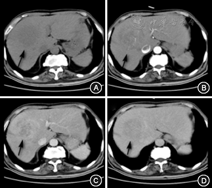

(1)病例特点:患者男性,69岁,因"胸闷不适5 d"于2015年8月6日就诊我院胸外科,正电子发射计算机断层显像(PETCT)提示:"肝右叶稍低密度肿块,考虑恶性可能大"(图1),以"肝占位"转入我科。既往史:否认肝炎病史。查体:无明显阳性体征。实验室检查:肿瘤标志物甲胎蛋白(AFP)、癌胚抗原(CEA)、CA19-9及其他生化检查未见明显异常。Child-Pugh分级为A级。B超及腹部增强CT均考虑恶性(图2,图3)。(2)治疗:手术行肝部分切除术,术中冰冻回报:考虑肝炎性肌纤维母细胞瘤。术后大体标本:呈黄白色、鱼肉状、质地较硬,似有包膜。(3)术后病理诊断为肝炎性肌纤维母细胞瘤。(4)预后:术后7个月门诊复查未见明显复发(图4),术后电话随访18个月未见明显复发表现,恢复良好。